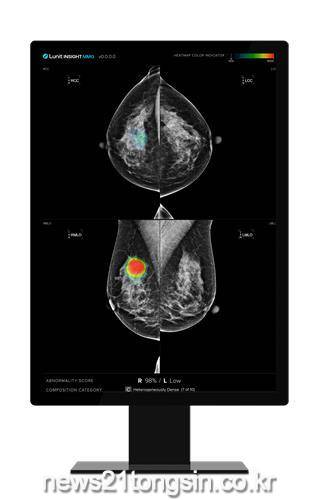

▲ 전주예수병원=루닛 유방촬영술 AI 영상분석 솔루션 사진

전북특별자치도 전주예수병원(병원장 신충식)은 유방촬영술 영상분석 AI 솔루션 ‘루닛 인사이트 MMG’를 도입했다고 2일 밝혔다.

서울대병원 등 공공의료기관에서 암 진단 과정에 루닛 AI 제품을 활용하는 조달청 ‘2024년 제2차 혁신제품 시범구매사업을 인지한 예수병원은 유방촬영술 영상분석 AI 솔루션 루닛 인사이트 MMG’을 본원에 선제적으로 도입해 유방암의 조기 발견과 진단 및 정확도 향상에 기여할 것으로 기대하고 있다.